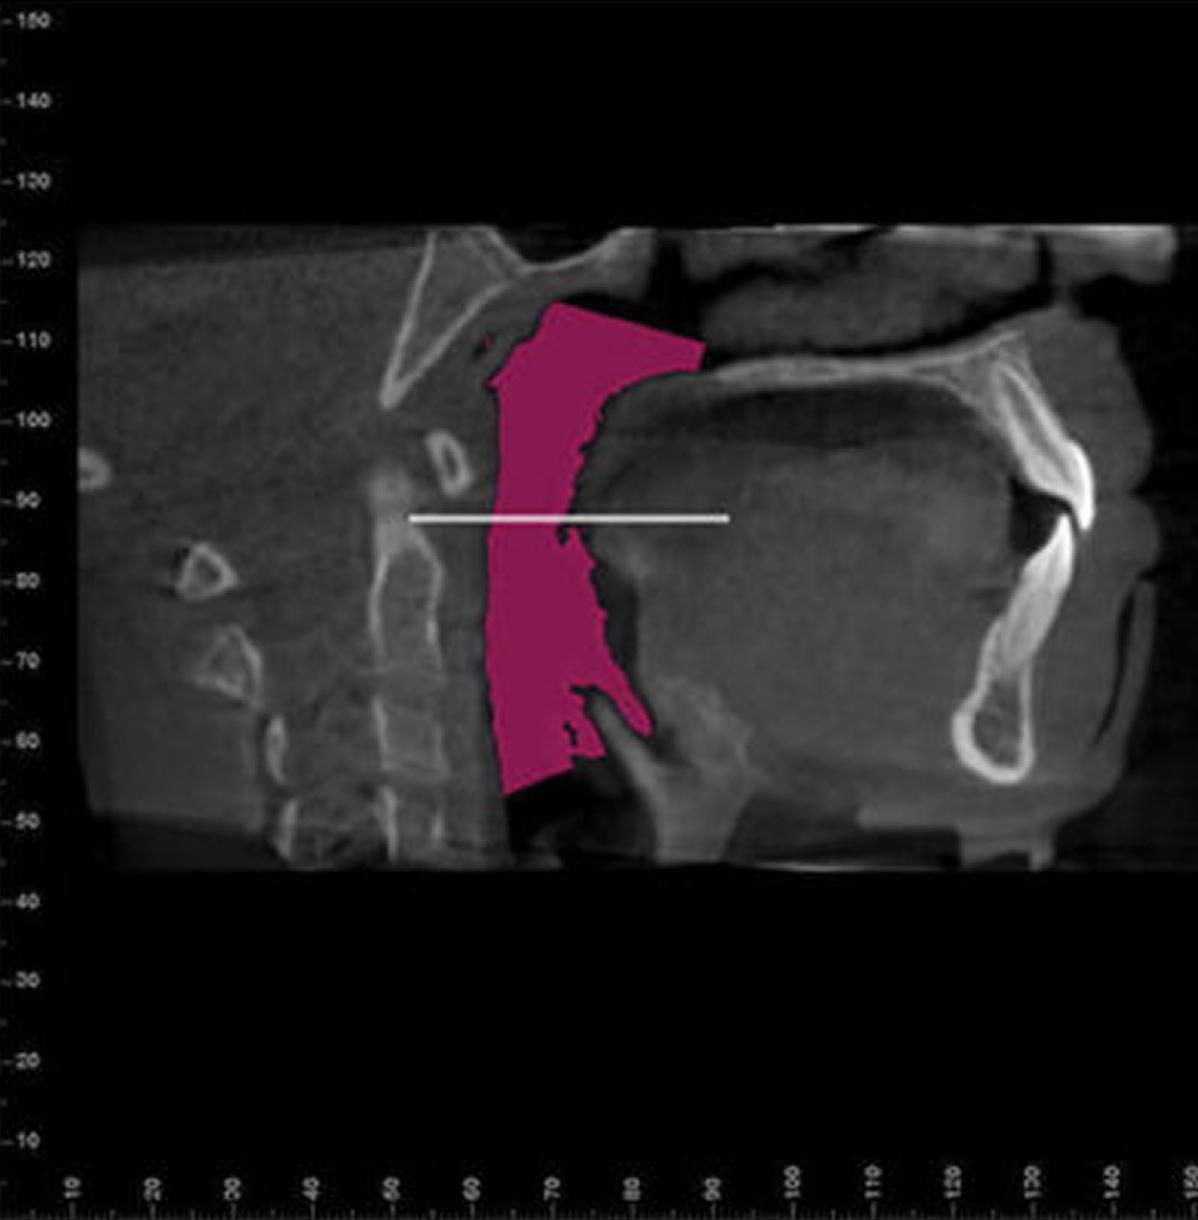

494% Airway Enhancement

We use an early comprehensive examination, sleep questionnaire, and medical history, as well as a low dose 3D I-CAT scan to diagnose sleep problems related to airway abnormalities.

867% Airway Enhancement